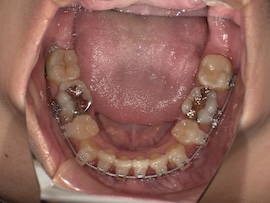

そこから1ヶ月後、